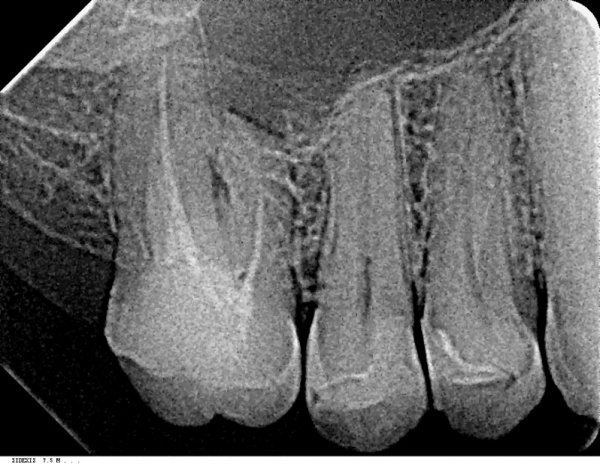

На верхней челюсти справа в районе зуба 6 образовалась небольшая припухлость, которая видна только со стороны щеки, при постукивании на сам зуб отдает болью, десна вокруг зуба не красная и не припухлая, воспаленной не выглядит, зуб залеченный.

Сделали снимок, врач, делавший снимок, направляет на удаление зуба по результатам снимка.

Возможно ли лечение этого зуба?